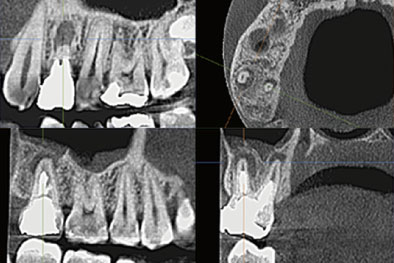

| 診断資料 | 単純撮影 レントゲン (2次元) |

CTレントゲン (3次元) |